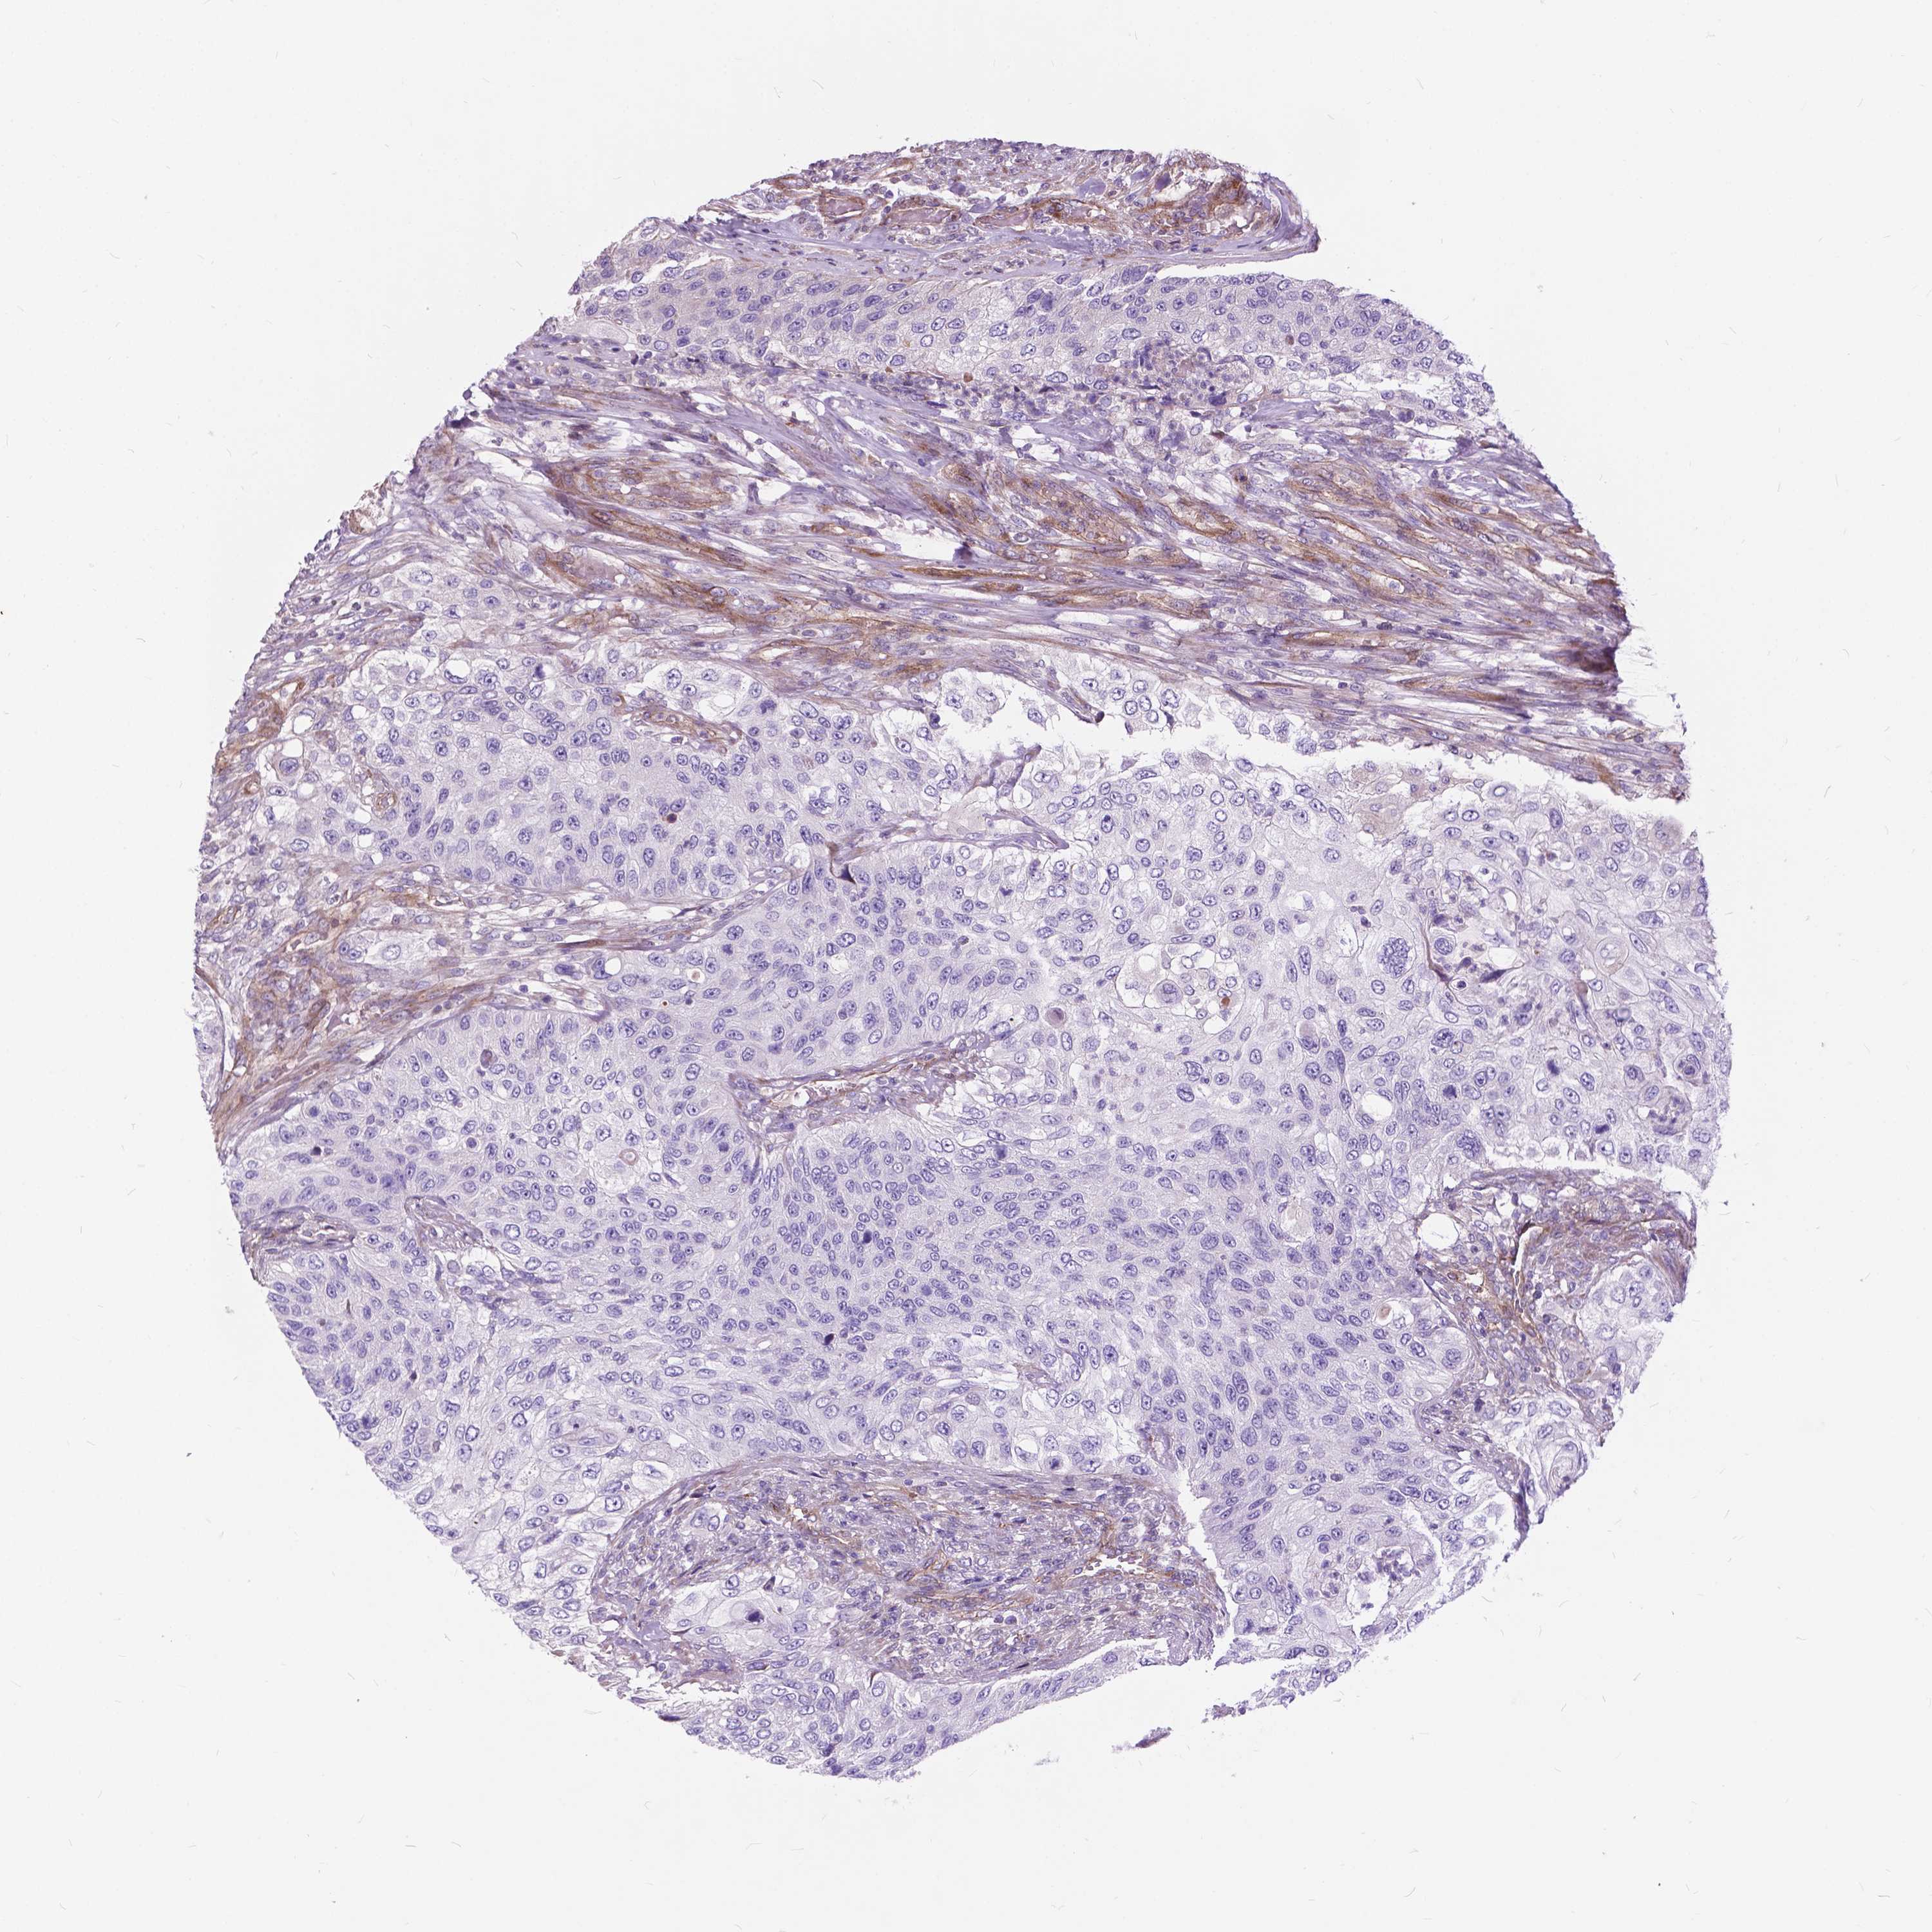

UROTHELIAL CANCER - Protein expressioni

A mouse-over function shows sample information and annotation data. Click on an image to view it in a full screen mode. Samples can be filtered based on level of antibody staining by selecting one or several of the following categories: high, medium, low and not detected. The assay and annotation is described here.

Note that samples used for immunohistochemistry by the Human Protein Atlas do not correspond to samples in the TCGA dataset.

Antibody stainingi

Antibody staining in the annotated cell types in the current human tissue is reported as not detected, low, medium, or high, based on conventional immunohistochemistry profiling in selected tissues. This score is based on the combination of the staining intensity and fraction of stained cells.

Each image is clickable and will lead to virtual microscopy that enables deeper exploration of all samples and also displays staining intensity scores, fraction scores and subcellular localization as well as patient and tissue information for each sample.

Antibody HPA067906

Antibody HPA074389

Urothelial carcinoma, High grade

Urothelial carcinoma, NOS

Urothelial carcinoma, Low grade